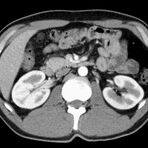

Abdomen (Bauch und Becken)

• Diagnostik von entzündlichen und tumorösen Erkrankungen der Bauchorgane

• Diagnostik von akuten Notfällen wie Darmverschluss, Hohlorganperforation oder Traumafolgen

• Darstellung der großen Gefäße zur Erkennung von Gefäßverschlüssen (z. B. Mesenterial - Arterienembolie oder Einengungen von Gefäßen (z. B. Nierenarterien)